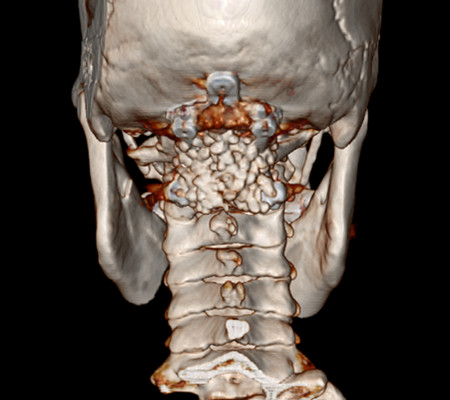

患者,女,53岁,以“颈肩部麻木、疼痛10月”入住神经外科一病区。该患者小脑扁桃体下疝畸形,颈椎先天发育也有异常。

主任刘增强、责任总医师巨涛等人就此病例进行了多次讨论。术前第一次运用先进的3D打印技术重塑了患者的寰枕部骨质及血管,证实了患者先天性寰椎后弓缺如。经过充分的术前准备,显微镜下切除了下疝的小脑扁桃体,结合3D打印结果,历时4小时完成了我院第一例后路减压+枕颈内固定术。患者术后3天下床活动,10天出院。

寰枕畸形是指枕骨底部及第一、二颈椎先天发育异常,除以骨骼为主的发育异常外,还合并有神经系统和软组织发育异常,包括扁平颅底、颅底陷入、寰枕融合、颈椎分节不全、寰枢椎脱位、小脑扁桃体下疝畸形等。